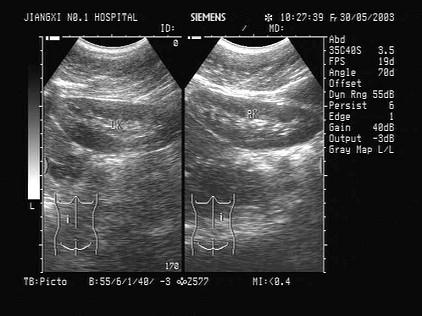

哪一类扫查可以显示以上肾脏图形?(?)A.横向扫查B.经肝纵向扫查C.肋缘下斜行扫查D.背部纵向扫查E.经侧腰部冠状扫查

问题 哪一类扫查可以显示以上肾脏图形?(?)

选项 A.横向扫查 B.经肝纵向扫查 C.肋缘下斜行扫查 D.背部纵向扫查 E.经侧腰部冠状扫查

答案 D